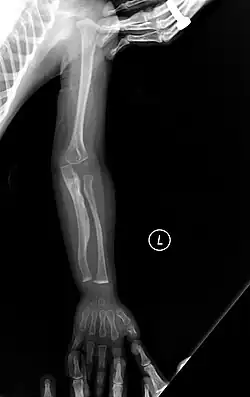

The main symptom of osteogenesis imperfecta is fragile, low mineral density bones; all types of OI have some bone involvement.[5] In moderate and especially severe OI, the long bones may be bowed, sometimes extremely so.[28] The weakness of the bones causes them to fracture easily—a study at the Endocrine Unit at the National Institute of Child Health in Karachi, Pakistan found an average of 5.8 fractures per year in untreated children.[29] Fractures typically occur much less after puberty, but begin to increase again in women after menopause and in men between the ages of 60 and 80.[1]: 486

OI type III causes osteopenic bones that fracture very easily, sometimes even in utero, often leading to hundreds of fractures during a lifetime;[24] early scoliosis that progresses until puberty; dwarfism (a final adult height frequently less than 4 feet or 120 centimetres); loose joints; and possible respiratory problems due to low rib cage volume causing low lung volumes.[5]: 1512

- Type V – Having the same clinical features as type IV, it can be clinically distinguished by observing a "mesh-like" appearance to a bone biopsy under a microscope. Type V can be further distinguished from other types of OI by the "V triad": an opaque band (visible on X-ray) adjacent to the growth plates; hypertrophic calluses (abnormally large masses of bony repair tissue) which form at fracture sites during the healing process; and calcification of the interosseous membrane of the forearm,[50] which may make it difficult to turn the wrist.[1]: 429 Other features of this condition may include pulled elbow, and, as in other types of OI, long bone bowing and hearing loss.[64] Cases of this type are caused by mutations in the IFITM5 gene on chromosome 11p15.5.[64][49] The separation of type V from type IV OI, its clinical type, was initially suggested even before its genetic cause was known, by Glorieux et al. in 2000.[50][65] Type V is relatively common compared to other genetically defined types of OI—4% of OI patients at the genetics department of the Brazilian Hospital de Clínicas de Porto Alegre were found to have it.[66]

Diagnosis is typically based on medical imaging, including plain X-rays, and symptoms. In severe OI, signs on medical imaging include abnormalities in all extremities and the spine.[97] As X-rays are often insensitive to the comparatively smaller bone density loss associated with type I OI, DEXA scans may be needed.[5]: 1514